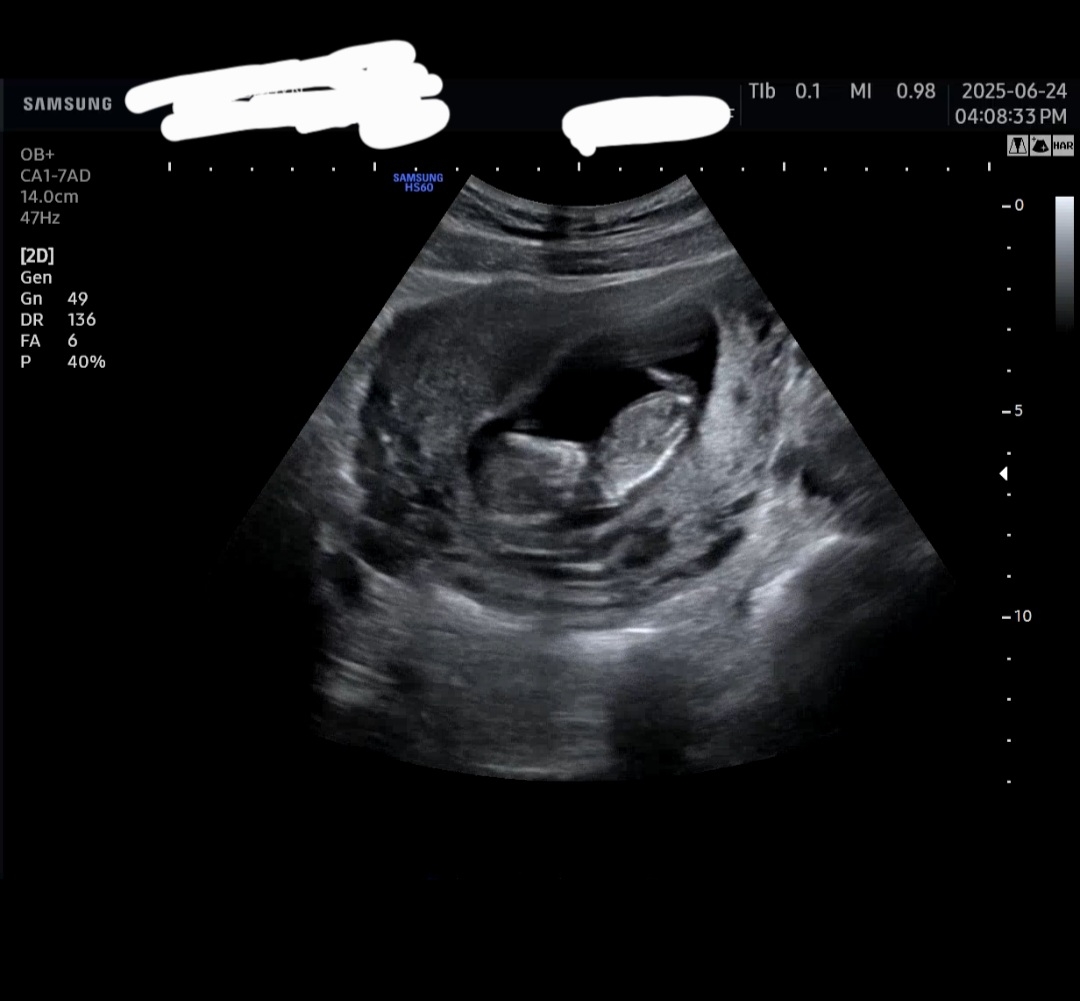

11주6일차 성별각도법

11주6일차된 똥글이맘입니당:) 벌써성별이너무궁금해서요ㅠㅠ 혹시 각도법 볼줄아시는분~!? 저희똥글이 왕자님일까요 공주님일까용🤭